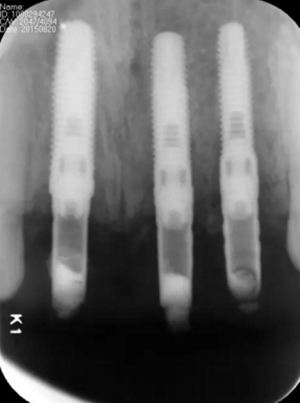

(2)即刻種植、即刻臨時修復(fù)。術(shù)中不翻瓣微創(chuàng)拔除牙根,牙槽 窩骨壁完整。在多級導(dǎo)板輔助下完成種植窩洞制備,植入Bego柱形種植 體,型號分別為:上頜右側(cè)中切牙位點4.1mm×15mm、上頜左側(cè)中切牙 位點?3.75mm×15mm、上頜左側(cè)側(cè)切牙位點3.25mm×15mm,扭矩均為 35N·cm。種植體與唇側(cè)骨壁間隙約2mm,植入Bio-Oss®Collagen骨膠 原。戴入橋用鈦臨時基臺,臨時冠就位順利,自凝樹脂口內(nèi)粘接后適當(dāng)修整 外形,充分磨光,調(diào) 至正中 、前伸 和側(cè)方 與對頜牙均無接觸。術(shù)后 根尖片顯示種植體位置、方向良好。

圖13 術(shù)后即刻根尖片

圖17 術(shù)后6個月根尖片

圖24 最終修復(fù)后即刻根尖片

(5)復(fù)查。種植體周圍骨水平穩(wěn)定,齦乳頭及齦高點位置穩(wěn)定,齦緣 曲線形態(tài)理想,唇側(cè)軟硬輪廓良好,功能滿意,修復(fù)效果符合預(yù)期。